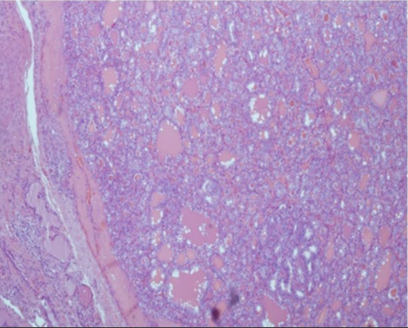

Each of the variants that compose it must be represented in at least 30% of the tumor cells. This combined pattern is made up of a predominant subtype, which corresponds to the histological variant with the highest percentage of tumor cells, and a secondary subtype, which is related to the subsequent histological variant with the following highest rate of tumor cells (Figure 2).2

Figure 2 The largest tumor was partially encapsulated and showed follicular pattern, with conventional papillary carcinoma cytology.